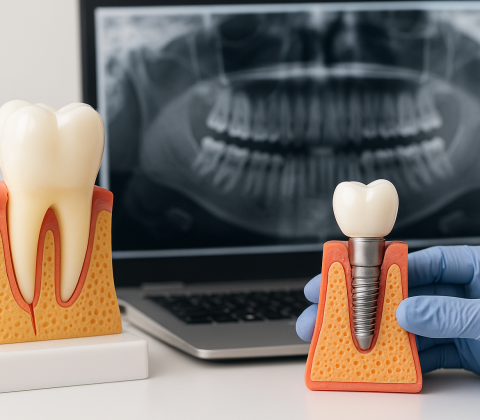

قیمت ایمپلنت دندان در سال ۱۴۰۴ + بررسی انواع برندها

قیمت ایمپلنت دندان در سال ۱۴۰۴ چقدر است؟ ایمپلنت دندان یکی از روشهای پیشرفته برای جایگزینی دندانهای از دست رفته است. قیمت ایمپلنت دندا

هزینه ایمپلنت دندان در سال ۱۴۰۴

ایمپلنت دندان یکی از روشهای نوین و ماندگار برای جایگزینی دندانهای از دست رفته است. این روش، نهتنها از نظر زیبایی بلکه از نظر عملکردی،